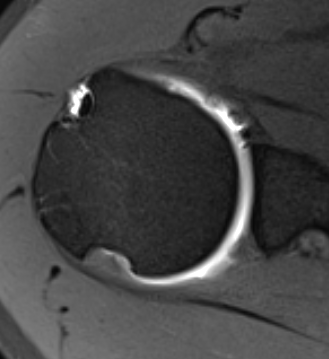

MRI

Normal humeral insertion of IGHL on left, HAGL with discontinuity of J sign on right

Hill Sachs variations